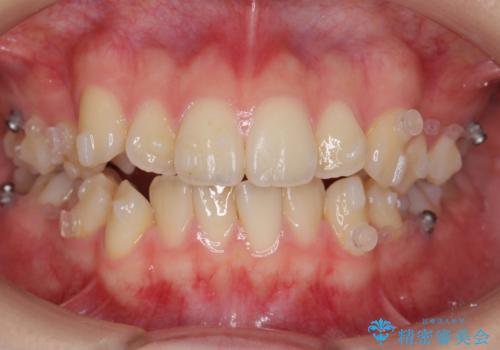

- 矯正装置

- インビザライン

- 3年6ヶ月

スペースを確保するために、歯をわずかに削る処置、奥歯を後ろに下げる処置(インプラント矯正)を行っています。

途中患者様のご都合で治療を中断していたため、長くかかっていますが、実質2年程度で終わる内容でした。